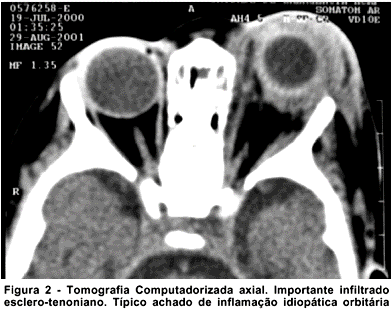

A TC revelou importante infiltração periescleral à esquerda, deslocando globo ocular para baixo e anteriormente. Não havia sinais de acometimento de seios da face (Figura 2).

A TC é de fundamental importância na diferenciação entre celulite orbitária e IOIA. No primeiro caso, geralmente há sinusopatia concomitante e as imagens sugerem infiltração difusa da gordura orbitária, descolamento da periórbita (abscesso subperiósteo) ou sinais de abscesso intra-orbitário. O quadro radiológico da paciente era distinto. Não havia sinusopatia e na órbita detectava-se uma infiltração predominantemente periescleral, achado típico das IOIA anteriores(6-7).